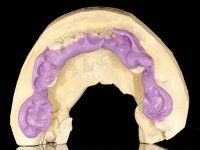

Patient was proposed extraction of the root of the 1.4 tooth, and immediate placement of an implant in its place. Confirmation of this rehabilitation proposal would always be dependent on prior accomplishment of a Computed Axial Tomography, in order to evaluate the available bone heritage. Provisionalization of the edentulous space would be done with a temporary fixed prosthesis bonded to adjacent teeth. This prosthesis would be prepared at the laboratory and would consist of an acrylic prosthetic tooth with an included metal wire that would serve as a retention element. In this way the esthetic problem was solved during osseointegration, avoiding the use of a removable prosthesis. The implant would eventually be rehabilitated with a screwed metal-ceramic crown.

A CT scan was performed to evaluate the available bone heritage and to choose the type and size of implant to be placed. An impression of both jaws was made in alginate, as well as intermaxillary recording for laboratory work on a provisional prosthesis. The provisional prosthesis was made by including a metal wire in a prosthetic tooth adapted to the edentulous space. The root was carefully removed and the implant was placed in the tooth socket corresponding to tooth 1.4. The remaining space between the walls of the alveolus and the implant was filled with regenerative material and then sutured. The prosthesis was previously adapted to the postoperative zone and was then bonded to adjacent teeth. Teflon was used to promote the best possible insulation. Bonding was done using photopolymerizable composite resin using the palatine and inter-proximal walls of the adjacent teeth. After 10 days, the suture was removed and one month later osseointegration was confirmed. Exposure of the implant and placement of the healing screw was performed after 10 weeks. The cervical portion of the provisional tooth had to be reduced to accommodate the healing screw. Stabilized peri-implant soft tissues were impressed using open tray technique with soft and regular consistency putty silicon. In the laboratory the work model was made, along with the choice of pre-fabricated components for the confection of a metal-ceramic crown screwed to the implant with the brand’s interface. Removal of the provisional bridge was done with great care not to touch the interproximal surfaces of the teeth adjacent to the edentulous space. The crown was screwed to the implant, and after imaging, the seating was given the final tightening with 35N of torque. The screw access hole was filled with Teflon and closed with composite resin. The patient manifested satisfaction with the aesthetic and functional rehabilitation achieved.